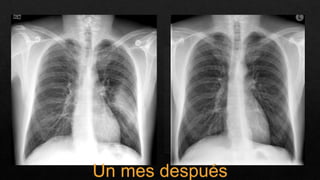

Un mes después